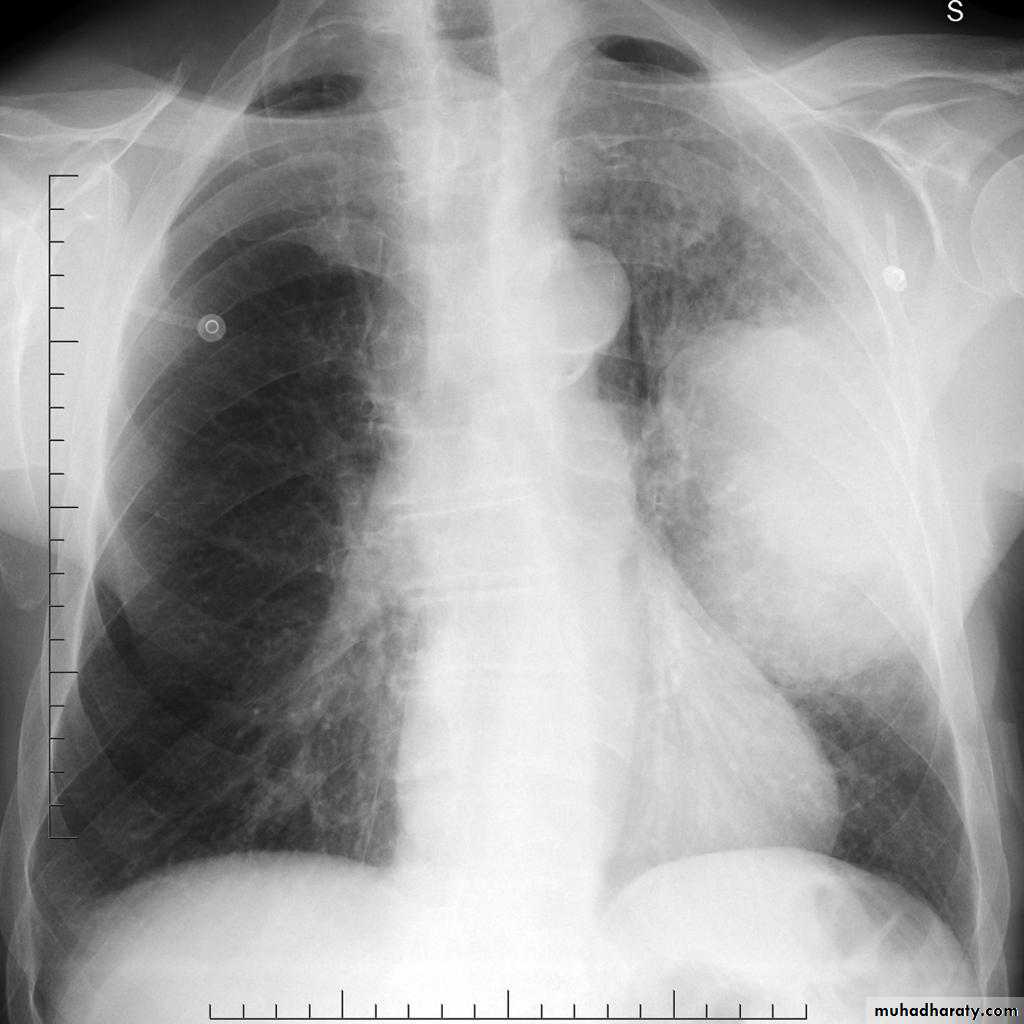

Pleural effusion

50.pleural effusion

51.pleural effusion .